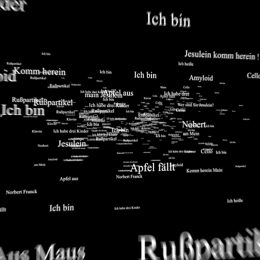

Bist du meine Frau?

In Zusammenarbeit mit der Hamburger Agentur Jung von Matt hat gate.11 einen Kinospot für die Alzheimer Forschung Initiative e.V. entwickelt. Er nimmt den Betrachter mit durch Fragmente und Gedankenwelten eines Alzheimer-Patienten. Ein virtueller Einblick, der die Dramatik dieser Krankheit einfühlvoll vermittelt.